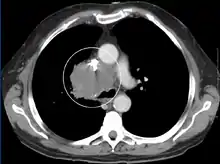

Diagnosis

The main techniques of diagnosing SVCS are with chest X-rays (CXR), CT scans, transbronchial needle aspiration at bronchoscopy and mediastinoscopy.[5] CXRs often provide the ability to show mediastinal widening and may show the presenting primary cause of SVCS.[5] However, 16% of people with SVC syndrome have a normal chest X-ray. CT scans should be contrast enhanced and be taken on the neck, chest, lower abdomen, and pelvis.[5] They may also show the underlying cause and the extent to which the disease has progressed.[5]